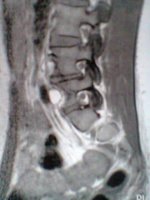

ich versuch es einfach mal...also ich hab seit ca 2 Jahren einen Bsv L4/L5 bislang ohne OP...

ich war 4 Wochen in reha danach habe ich die Wiedereingliederung gemacht und arbeite seitdem wieder in Vollzeit ( seit September 2011 ) jetzt seit 1 Monat habe ich wieder starke schmerzen und dazu gekommen ist mein Steißbein,kann kaum sitzen und beim aufstehen tut es höllisch weh

arbeiten geh ich zur zeit nur 5-7 Std danach geht nicht mehr.....nehme seit ca 7 Monaten Targin 20mg/10 mg 3 mal am Tag...so wirklich lange helfen die leider auch nicht mehr...Heute war ich beim MRT könnte jemand von euch mir die ein bissel beschreiben????